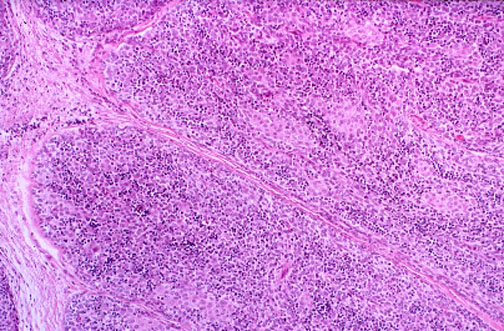

At low power, this thymoma contains epithelial elements, with a background of small round lymphocytes that are not neoplastic themselves. About half of all thymomas occur in association with myasthenia gravis.